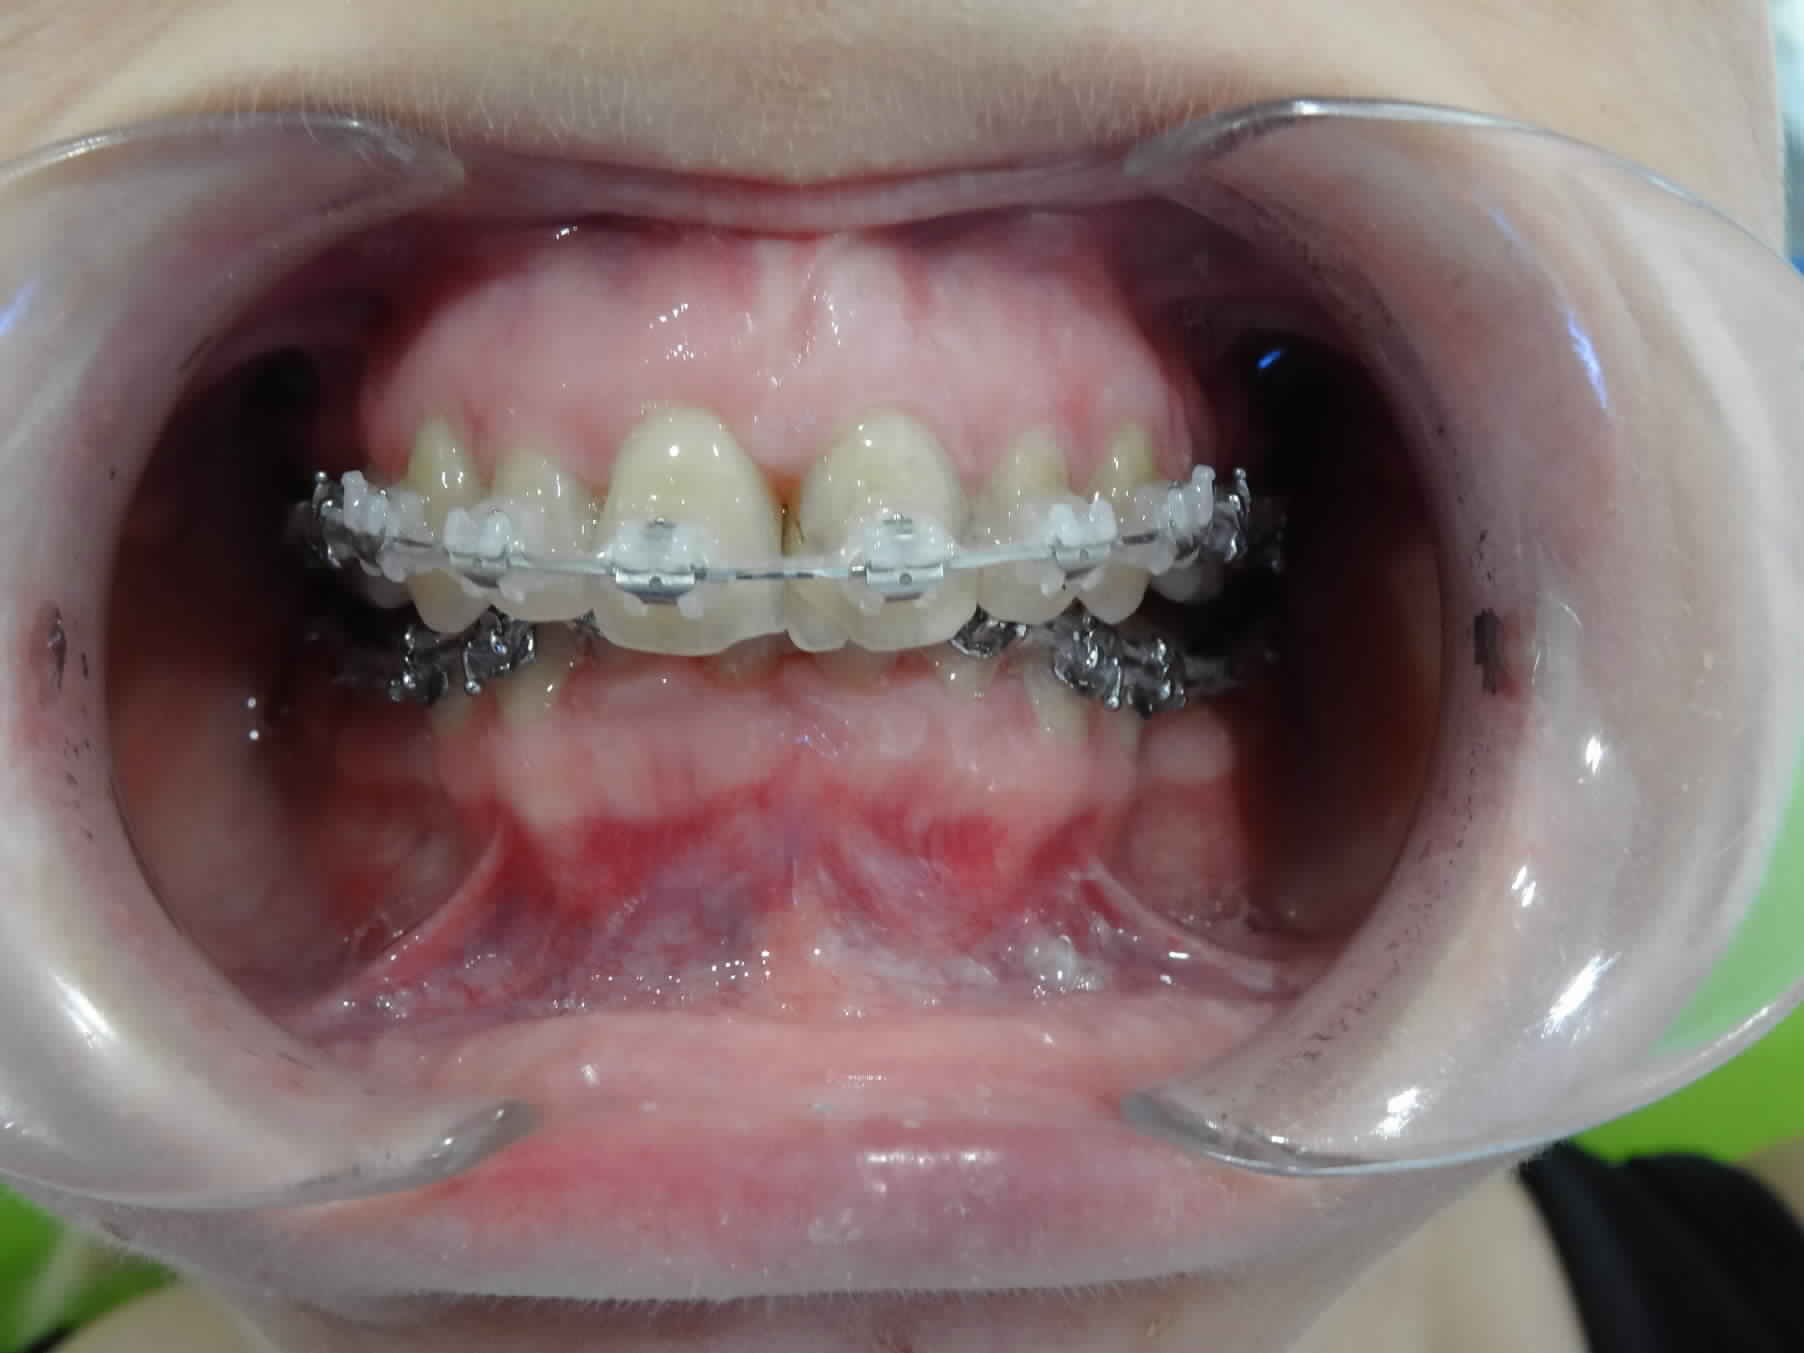

je sollicite vos avis sur ce cas adulte en cours de traitement, avec avulsion des 5 , la supraclusion et la courbe de spee s'est accentuée au cours de la fermeture des espaces , je suis en autoligaturant AO avec des fils actuellement en 14.25 Cuniti ?

Dans votre cas vous avez créer une flexion de l'arcade maxillaire et mandibulaire en essayant de fermer les espaces par chaînette sur un arc qui n'est pas stable (14/25 Cooper niti).

Vous avez créer des versions des couronnes, fermant ainsi les espaces des 5 .

Ce que tu montres là est un cas d'école et il serait intéressant de bien voir et comprendre ce qui s'est passé pour éviter que ce genre plaisanterie ne se reproduise pas.

1 Pourquoi et comment cela a-t-il pu évoluer en supraclusie ++ ?

1 Il suffit de regarder l’angle que font la prémolaire et la canine par rapport au plan général d’occlusion (surtout la canine sur la vue clinique).

Observe la position de leurs braquets, induite par la distoversion des dents liée au recul (j’écris « braquet » parce que c’est un mot français que les anglo-saxons qui nous l’ont piqué pour nous le retourner perfidement avec une orthographe frelatée).

Tu constates que ce sont ces braquets et eux seuls qui orientent le fil en direction occlusale du côté mésial, ce qui entraine l’égression des incisives.